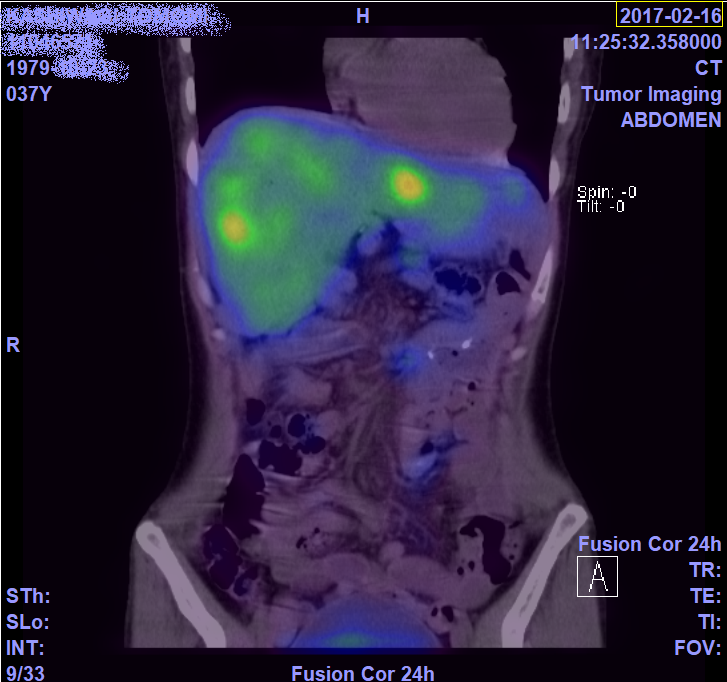

2月のCTとオクトレオスキャンの画像。

これが無治療だと半年で肝不全なっちゃう?肝臓らしいよ。

ちょっと肝臓腫れてるらしいけど、わからないね…

わかるかな?CTは白いやつが全部腫瘍。

オクトレオスキャンは光ってるやつ(二枚目の大きい濃いオレンジは違うよ)

参考にどうぞ。